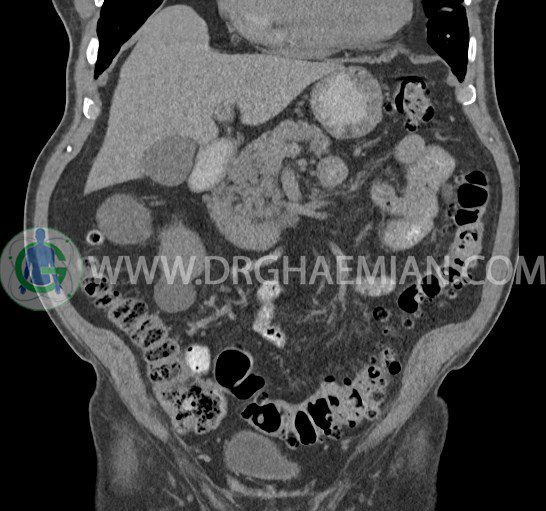

سی تی اسکن لگن یکی از روش های تصویربرداری با سی تی اسکن است. این روش با استفاده از تشعشعات تصاویر عرضی از ناحیه شکمی ایجاد میکند. در این کیس ديورتيكولوزيس، کیست های کورتیکال در هر دو کلیه، لنفادنوپاتی، کلسیفیکاسیون دیواره آئورت و شریان ایلیاک، تغییرات DJD ناحیه توراکولومبار و پروستات بزرگتر از عادی دیده می شود.

در سي تي اسکن اسپيرال شکم و لگن با و بدون کنتراست خوراکی و وريدی (مولتي ديدکتور 16 با مقاطع ظريف و بازسازي هاي ساژيتال و کرونال):

– کيست هاي کورتيکال ساده به قطر 5 mm تا 50 mm در کليه راست و به قطر 5mm تا 55 mm در کليه چپ

– توده ايزودنس به ابعاد mm 17 x 28 در پره ائورت مجاور قسمت تحتاني D3 دئودنوم مطرح کننده لنفادنوپاتي و با احتمال کمتر آنوريسم ترومبوزه (نيازمند مطابقت سونولوژيک)

– کلسيفيکاسيون ديواره آئورت و شريان ها ايلياک همراه با نشانه هاي ترومبوز مورال در بيفورکاسيون ائورت با امتداد به پروگزيمال هاي شريان هاي ايلياک

– ديورتيكولوزيس در کولون نزولي وسيگموئيد

– تغييرات DJD در ناحيه توراکولومبار و

– پروستات به ابعاد mm 45 x 54، بزرگ تر از نرمال

مشهود است.